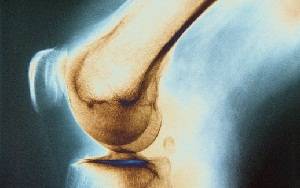

Локализации туберкулезного поражения распределились следующим образом: проксимальный эпиметафиз большеберцовой кости - 6, таранная кость - 4, пяточная кость - 3, дистальный эпиметафиз бедра - 3, проксимальный эпиметафиз бедра - 2, дистальный эпиметафиз большеберцовой кости, тело подвздошной кости и изолированное поражение шейки бедра - по 1. Всем больным проводили стандартную специфическую терапию тремя противотуберкулезными препаратами на протяжении 2 мес после операции, затем двумя препаратами - до 10 мес. Рентгенологический контроль осуществляли на сроках 1, 2, 4, 6 мес и 1 год после операции. Минимальный срок послеоперационного наблюдения составил 2 мес, максимальный - 20 мес. Динамику адаптации и перестройки пластических материалов оценивали по рентгенограммам визуально, не прибегая к методам цифрового анализа.

Гладкое послеоперационное течение без обострений и рецидивов отмечено у всех детей, в том числе исходно имевших свищи. При визуальной оценке проведенных в динамике рентгенограмм ни в одном случае применения новых пластических материалов нами не выявлено их резорбции. Кроме того, ни в одном случае мы не наблюдали реакций перифокальной кости ни склеротического, ни остеолитического характера. При применении Тутопласта® "Губчатый блок" в 3 случаях уже через 6 мес. биоимплантат из губчатой кости практически полностью перестраивался без четких границ кости донора и реципиента, что позволяло к этому сроку разрешать физиологические нагрузки. При применении ВСР имплантат также хорошо адаптировался, однако, и в отдаленные сроки кость в зоне пластики сохраняла значительно более высокую плотность.